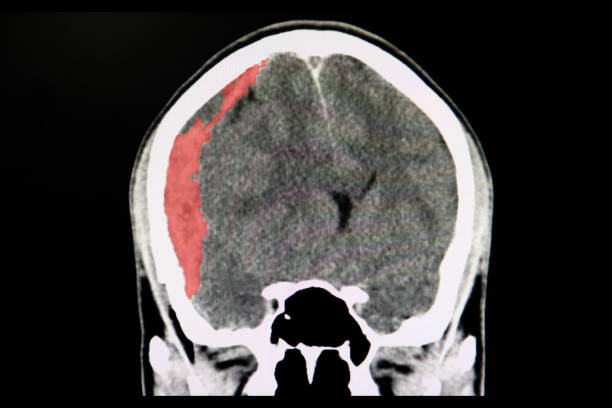

뇌출혈은 뇌안에 있는 혈관에서 출혈이 발생하여 뇌조직이 손상을 입는 질환이며, 중증의 뇌혈관질환 중 하나입니다. 일반적으로 고혈압, 동맥류, 혈관 기형, 혈전 등의 이유로 혈관이 파열하거나 뚫리면서 발생합니다.

고혈압은 뇌출혈을 일으키는 가장 일반적인 원인 중 하나입니다. 고혈압은 혈관벽을 약화시켜 혈관이 파열하기 쉽게 만들기 때문입니다. 또한, 혈관에 생긴 약간의 이상증상이나 동맥류, 혈관 기형 등도 뇌출혈의 원인이 될 수 있습니다.

뇌출혈은 갑작스러운 발작, 의식 잃음, 경련, 혼란, 언어 장애, 편마비 등의 증상을 일으키며, 이러한 증상이 발생하면 즉시 의료진의 진료를 받아야 합니다. 뇌출혈은 치료가 지연되면 심각한 후유증을 일으킬 수 있으므로, 조기 발견과 적절한 치료가 필요하기 때문에 이번 시간에는 뇌출혈 전조 증상에 대해 자세히 알아보겠습니다.